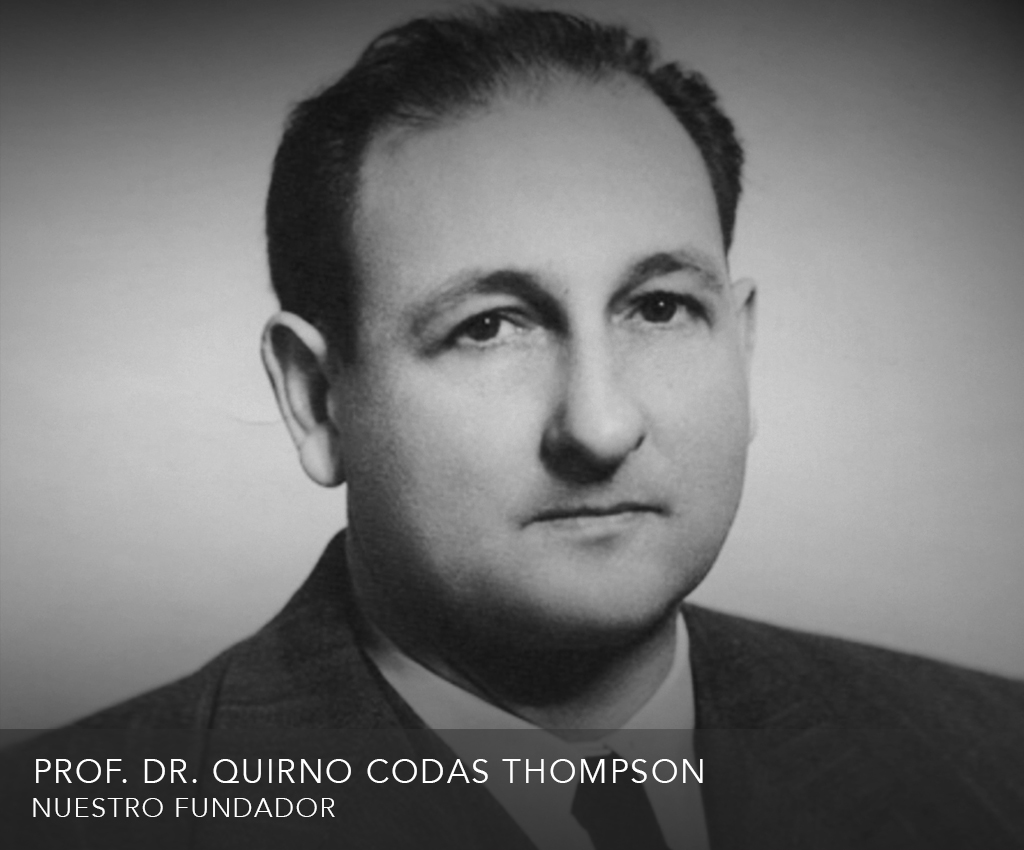

Sus conocimientos científicos trascendieron las fronteras del Paraguay. Fue Profesor de Radiología invitado por diversas universidades latinoamericanas donde dictó clases. Fue miembro correspondiente honorario de sociedades científicas latinoamericanas y mundiales, y obtuvo en el año 1971 su máximo galardón con la “Medalla de Oro” del Colegio Interamericano de Radiología, distinción otorgada cada 4 años al Radiólogo más distinguido de toda América.

El Dr. Codas también fue autor de varios libros entre ellos, el más conocido “Radiología del estómago” se encuentra en bibliotecas de varias universidades del mundo. Nunca dejó de incorporar al país tecnología de punta, y es digno mencionar que gracias a su tezón innovador, Paraguay fue varias veces el primer país en Sudamérica en contar con equipos de última generación que recién aparecían y que no existían en otros países.

Entre los ejemplos más representativos podemos citar que en 1945 incorpora el primer servicio de Radioterapia del Paraguay. En la década del 50 otros equipos de Radiología Diagnóstica como la Dental y la Cine Radiografía. En 1960, la primera Bomba de Cobalto 60 para Radioterapia, también equpos de Radioterapia Superficial y en el Área de Diagnóstico, nuevos equipos que aumentaron la capacidad de trabajo en número y calidad del Instituto Codas Thompson.